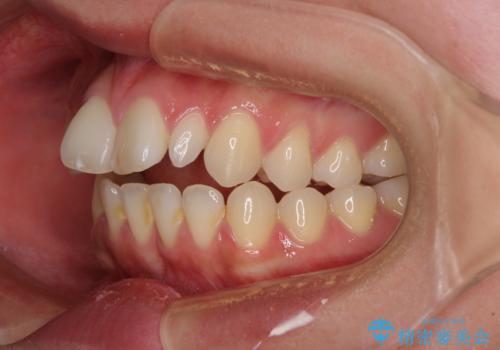

飛び出した前歯 インビザラインを用いた抜歯矯正治療

- 前方に飛び出した前歯を気にして来院された患者様です。

上下前歯同士の距離が離れているため、上顎左右第一小臼歯2本を抜歯することで前突を改善することとしました。

しかしながら、左右ともに側切歯が矮小歯であるため、矯正治療で矮小歯前後にスペースを作り、矯正治療後にオールセラミッククラウンにて補綴治療を行うこととしました。